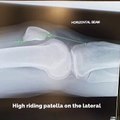

Joint injections of hyaluronic acid help to lubricate and cushion, but when you get the right molecular weight in high concentration, you can also achieve biosynthesis of endogenous hyaluronic acid, creating a healthier synovial fluid.